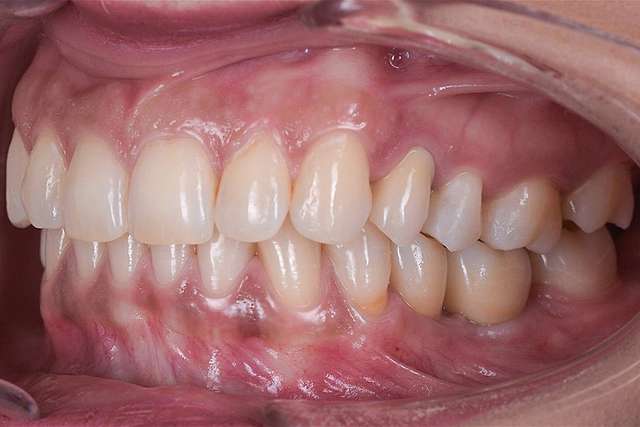

Ghidurile chirurgicale sunt utilizate pentru o siguranta si o precizie sporita in cazurile complexe care necesita tratamentul cu implanturi dentare. Ghidurile sunt printate 3D, conform planificarii digitale a chirurgiei, folosind un software specializat si radiografia 3D a pacientului. (computerul tomograf)

Pentru un rezultat estetic ideal, design-ul final trebuie sa fie intotdeauna referinta pentru chirurgie. Design-ul si computerul tomograf al pacientului sunt compilate pentru a primi pozitia ideala a implanturilor dentare

Chirurgia ghidata este sigura si precisa. Ghidul chirurgical este recomandat in cazurile cu un nivel ridicat de dificultate, sau in cazurile complexe, pentru a minimiza riscurile si complicatiile.

Cand procedura insertiei implanturilor dentare se realizeaza cu ajutorul chirurgiei ghidate, chirurgia in sine este mai simpla, iar trauma este mai redusa, in special asupra tesuturilor moi. Astfel, obtinem o vindecare mai rapida, si un comfort sporit post operator.